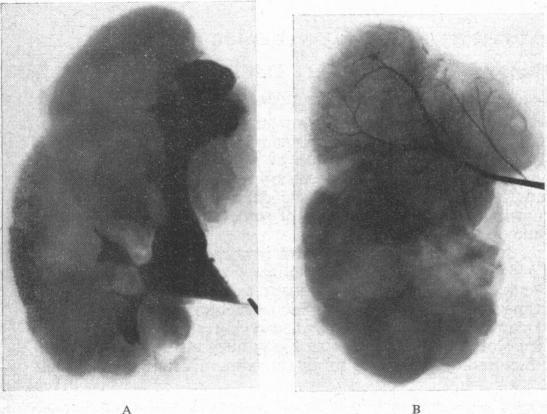

Renal arteriography in hypertension.

Proc R Soc Med. 1957 Jul;50(7):539-43. doi: 10.1177/003591575705000720.